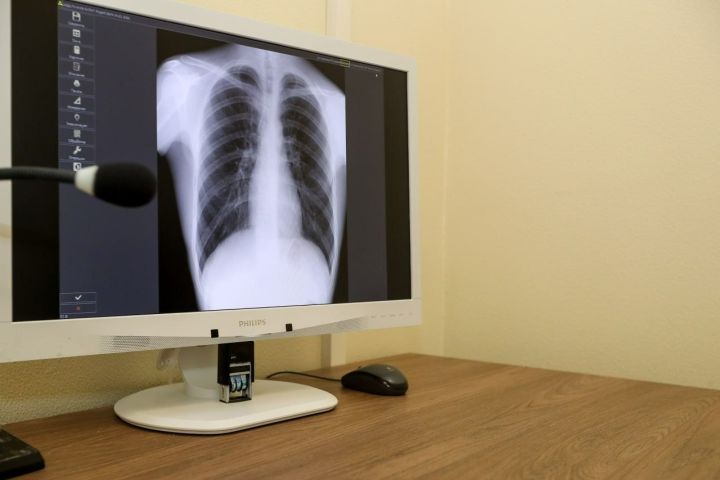

Профилактика рака легких: современный взгляд и перспективы

Отказ от курения, защита от вредных факторов окружающей среды, здоровый образ жизни и регулярные медицинские проверки - ваше главное оружие в борьбе с этим страшным заболеванием

Рак легких остается одним из самых опасных видов онкологических заболеваний. По всему миру он занимает лидирующие позиции по частоте смертности среди рака. Однако ученые и врачи неустанно работают над тем, чтобы помочь людям избежать этого заболевания. В основе успешной борьбы с раком легких лежит профилактика — комплекс мер, направленных на предупреждение развития болезни. О том, как уберечься от рака легких, о новшествах и перспективах в этой области рассказали специалисты Республиканского центра общественного здоровья и медицинской профилактики — заместитель главного врача Рушана Валиева и врач Никита Чумарев.

5. Медицинские осмотры и скрининг

Для людей из групп риска (курильщики старше 50 лет, работники вредных производств) врачи рекомендуют прохождение скрининга — специального обследования, чаще всего с помощью низкодозной компьютерной томографии (КТ). Это позволяет выявить рак на ранней стадии, когда лечение наиболее эффективно.